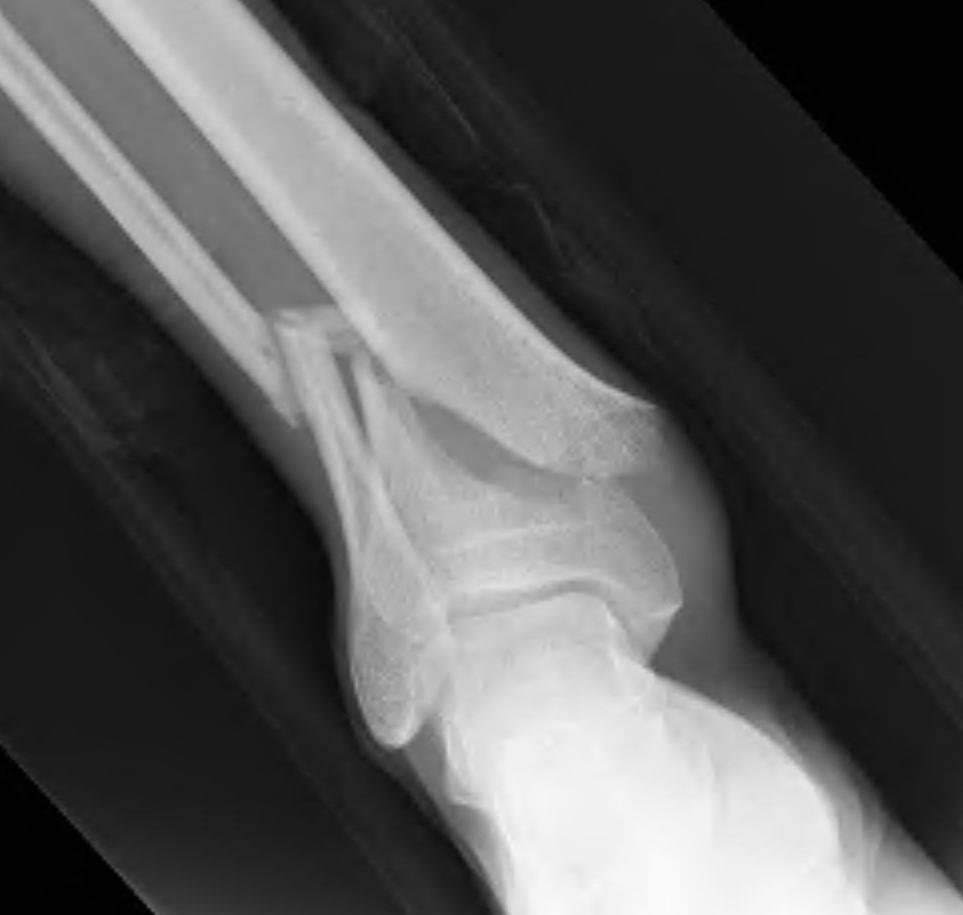

Temporary External fixation

Indications

- significant swelling

- significant displacement / non controlled in cast

- significant wounds, need for soft tissue coverage

Technique

- two pins proximal tibia

- trans-calcaneal pin

AO Trauma Ankle Bridging Delta Frame